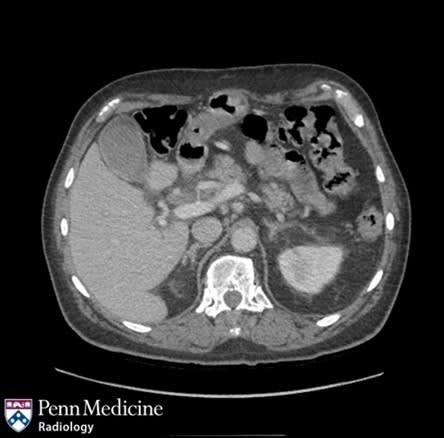

A 34-year-old man in Mexico suffered severe abdominal pain seconds after drinking a smoky cocktail infused with liquid nitrogen. He was found to have a ruptured stomach with pneumoperitoneum and underwent laparoscopic repair using tissue from his abdomen, recovering and being discharged three days later. The report highlights the dangers of consuming liquid nitrogen in beverages, which can rapidly expand as it warms, and notes that safety hinges on allowing the nitrogen to vaporize completely; the Leidenfrost effect may have helped shield tissue from cold burns.